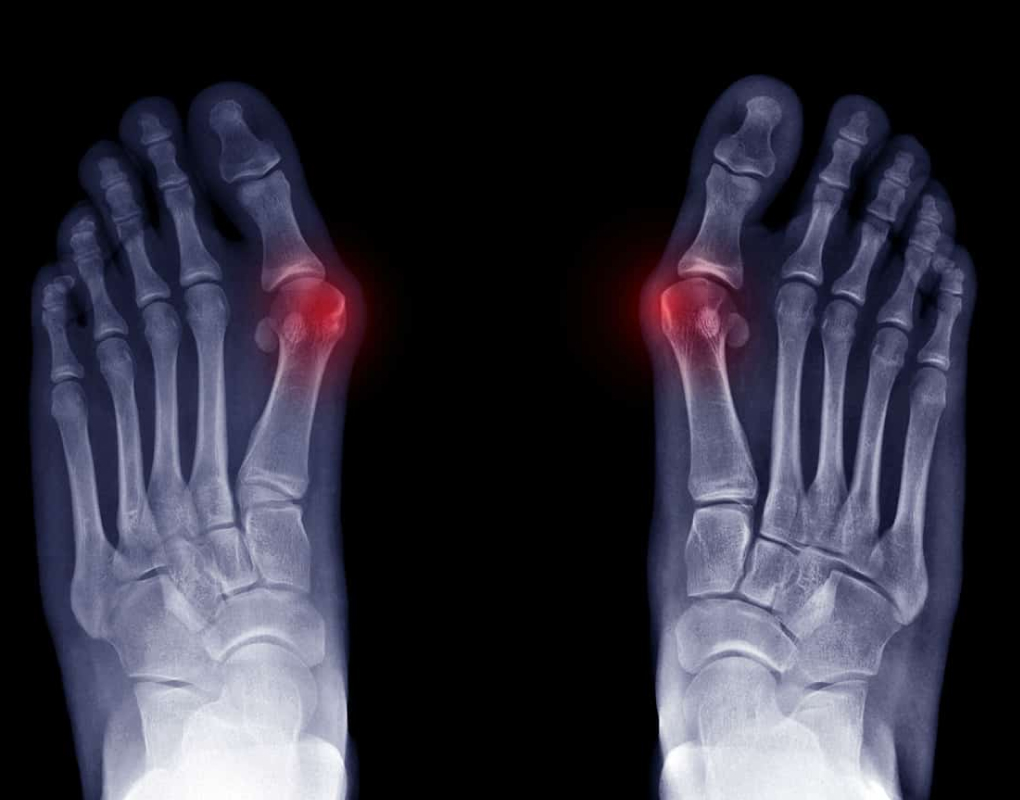

Bunions are a common foot problem that is accompanied by symptoms including pain and a bony growth that turns into a large lump.

Regular checks and x-rays are recommended to prevent joint damage. Treatment options include changes in foot wear, orthotics, regular exercise, padding and active modifications such as standing or walking for long periods of time.

A bunion is a bony bump that forms at the base of the big toe where it meets the foot. The big toe may start to angle toward the second toe, and you may notice a visible lump, redness, swelling or rubbing in shoes. If you are unsure, a podiatry assessment can confirm whether you have a bunion and how advanced it is.